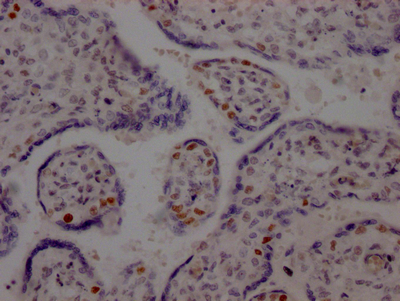

IHC image of CSB-RA877322A0HU diluted at 1:100 and staining in paraffin-embedded human lung cancer performed on a Leica BondTM system. After dewaxing and hydration, antigen retrieval was mediated by high pressure in a citrate buffer (pH 6.0). Section was blocked with 10% normal goat serum 30min at RT. Then primary antibody (1% BSA) was incubated at 4℃ overnight. The primary is detected by a Goat anti-rabbit IgG polymer labeled by HRP and visualized using 0.05% DAB.